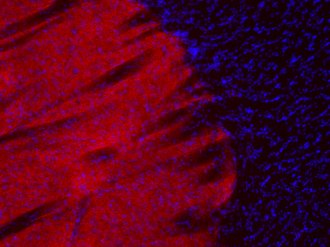

ICC: 1 : 500 gallery

IHC: 1 : 500 gallery

IHC-P: 1 : 1000 gallery

Immunocytochemistry (ICC) on 4% PFA fixed cells. Immunoreactivity is usually revealed by fluorescence. Some antibodies require special fixation methods. For details, please refer to the “Remarks” section.

Immunohistochemistry (IHC) on 4% PFA perfusion fixed tissue with 24h PFA post fixation. Immunoreactivity is usually revealed by fluorescence or a chromogenic substrate. Some antibodies require special fixation methods or antigen retrieval steps. For details, please refer to the ”Remarks” section.